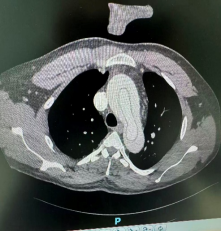

近日,广元市第一人民医院先后接诊了两名A型主动脉夹层患者。他们的年龄均在50岁左右,且体型肥胖,有长期高血压史但均未规律服用降压药。主动脉夹层如同血管内膜被撕裂,血液在血管壁夹层中冲击形成“假腔”,血管壁仅剩一层薄弱外膜支撑,宛如体内埋藏了一颗“不定时炸弹”,随时可能破裂导致猝死。

一切准备就绪后,手术团队为第一位患者实施了“主动脉根部成形+升主动脉置换+全弓置换+弓上三分支重建+远端支架植入术”。该手术属心外科领域最复杂、技术要求最高的术式之一,需在深低温停循环的有限时间窗内,精准重建心脏输出的“生命主干道”。手术历时5个多小时顺利完成,患者术后恢复良好,已康复出院。

后续,手术团队为另一位患者实施了技术难度更高的“主动脉根部成形+主动脉瓣成形+升主动脉置换+全弓置换+弓上三分支重建+远端支架植入术”。该手术在置换病变血管的同时,成功修复了患者自身的主动脉瓣,既清除了致命隐患,也避免了术后终身抗凝,显著提升了患者的远期生活质量。该患者术后转入ICU监护,病情稳定后现已转回普通病房继续治疗。